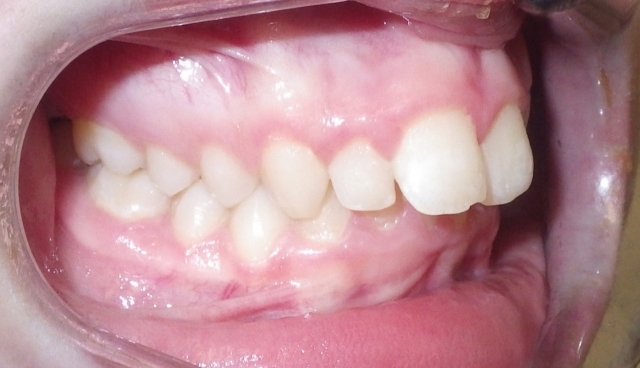

Monitoring the erupting dentition can help the patient receive the correct timing for intervention. A panoramic image as a screening procedure can confirm if there is adequate space for full permanent tooth eruption, if the eruption sequence is normal and if there are any impediments to eruption present. In Class II growth patterns in particular, noting the time for eruption of the upper second molar can make a difference in the ease of establishing the Class I molar relationship. Using methods to increase the arch length by distalizing the upper first molar can provide the dual benefit for adequate eruption space and the molar correction. (Fig. 2 and 3)

The arch width for a Class II pattern is important to note since it will play a role with both proper alignment and with proper buccal coordination of the molars. During advancement of the lower arch with growth modification, the width discrepancy between upper and lower molars will increase. The wider lower posterior molar width will advance and often result in an end-to-end buccal cusp relationship. With more severe maxillary constriction, a crossbite can result.

There are several ways to expand the molar width with arch wires and auxiliary wires. Full arch expansion can be accomplished with rapid palate expansion. Expansion can have the added benefit of decreasing the narrow buccal corridors (Fig. 9)

The arch form is also an important factor to evaluate in a Class II pattern. If the upper arch form is narrow, the upper incisors are more protrusive with an increased overjet. (Fig. 5 and 6) The maxilla appears “V” shaped from the occlusal view. (Fig. 7 and 8) The lower arch form is often broader because it is set more posterior in a wider area of the upper arch. If the full upper arch form is not expanded, there will be an excess overjet that remains. Imagine trying to align a round circle into the peak of a triangle. If the full arch is expanded with an expander, the upper and lower arches can coordinate to a normal overjet. (Fig. 4)